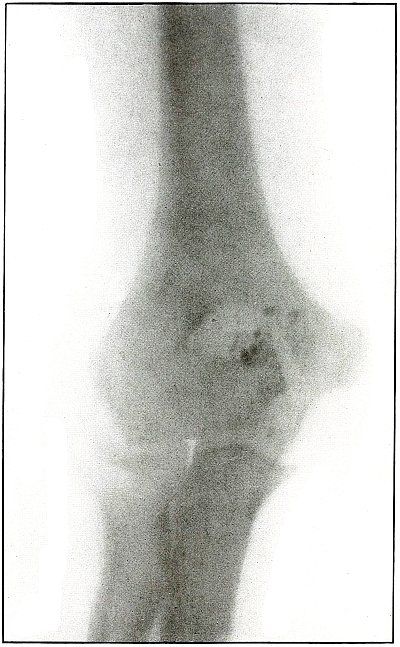

17. Gunshot fracture, elbow 44

18. Gunshot fracture, elbow 46

19. Gunshot fracture, elbow 48

20. Gunshot fracture, elbow 50